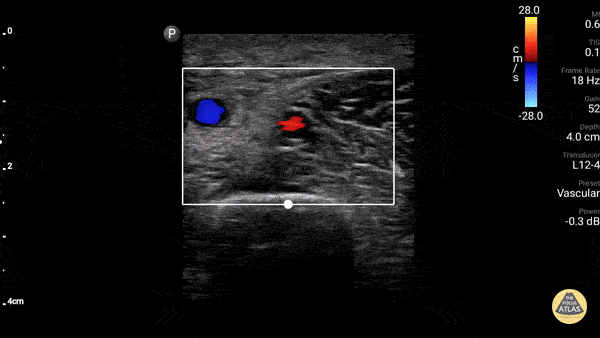

Vascular - Axillary Vein (Normal Compressible)

Axillary vein thrombus ruled OUT in a patient with arm swelling. Doppler used to highlight vein and artery. Dr. Gordon Johnson